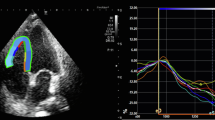

Myocardial function was evaluated by 2D-STE with a quantitative analysis function of myocardial deformation. The end of diastole was defined as the peak R wave of the electrocardiogram, while the end of systole was defined as the time at which the aortic valve closed. Endocardial borders were monitored within the frame of 2D images at the end of systole. The epicardial border was determined by adjusting a wide myocardial width. The midpoints between the endocardial and epicardial borders and the middle myocardial border were determined automatically. If necessary, manual adjustments were made to ensure correct tracking and to involve all LV wall thickness for 2D speckle viewing width. The analysis of LV-GLS was performed from the apical four-, three-, and two- chamber images. In the analysis, the QLAB-CMQ software program Philips Epiq 7C was used. Peak systolic strain measurements of each segment were automatically taken by a software (analysis) program. Longitudinal strain values of a total of 18 segments were obtained, and the mean value was determined as the global strain [16]. The analysis of RV-LS was performed from the apical four-chamber view. After tracing the RV endocardial border, the region of interest was automatically generated, and manual corrections were subsequently performed to fit the thickness of the RV myocardial wall. The RV free wall was automatically divided into three segments: basal, mid, and apical. RV-LS was calculated as the mean of the strain values of the three segments of the RV free wall. Segments that could not be tracked after manual adjustment by the operator were excluded.

Using 2D-STE, the conventional echocardiography parameters and GLS parameters of the three groups were compared. A comparison of the LVEF, stroke volume (SV), cardiac output (CO), LVEDD, LVESD, LV mass, WMSI, left atrium (LA), the E/A ratio, and the E/e’ ratio of the three groups revealed no statistically significant difference. The LV-GLS values of the control, non-severe, and severe groups were − 19.4 ± 1.6%, − 16.7 ± 1.3%, and − 14.5 ± 1.8%, respectively, and there was a statistically significant difference among the three groups (p < 0.001). It was observed that the sPAP value, which is one of the conventional parameters, was statistically significantly higher in the severe group compared to the other groups. In addition, the RV diameter was found to be higher in the severe group compared to the other groups, The RV-LS values of the control, non-severe, and severe groups were − 27.3 ± 3.1%, − 20.5 ± 3.2%, and − 17.2 ± 2.3%, respectively, indicating a statistically significant difference among the groups (p < 0.001) (Fig. 1).